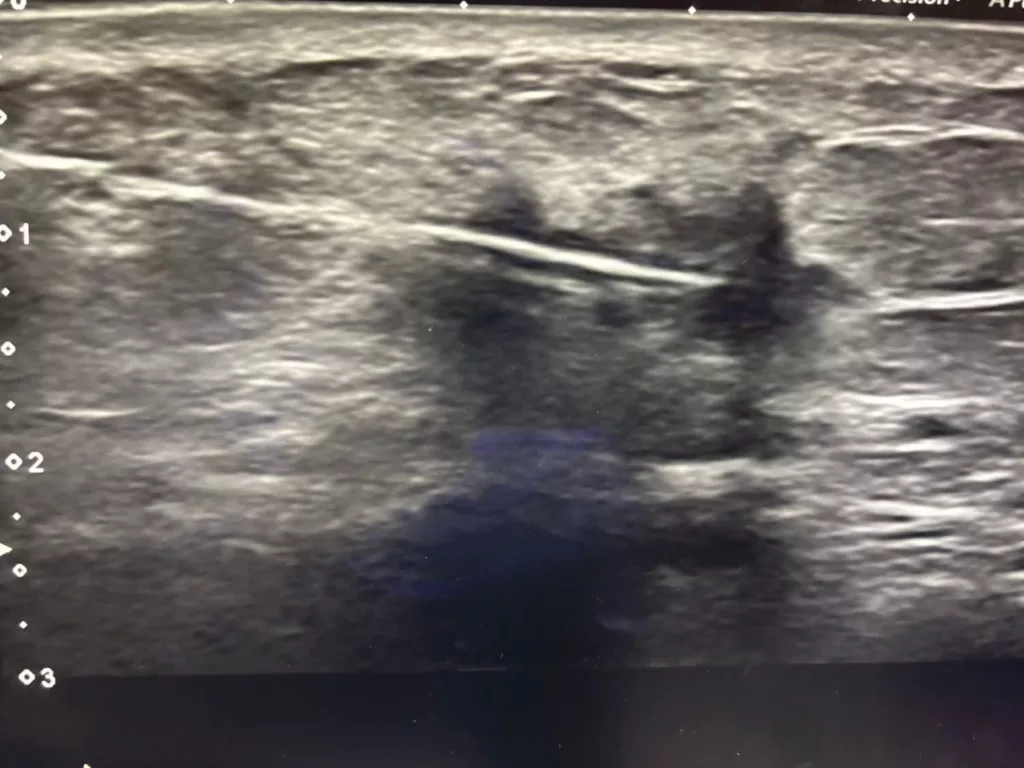

“Gambar ni adalah gambar ultrasound ketulan yg tumbuh di payudara. Memang nampak ciri kanser yang malignant dgn permukaan menggerutu (irregular outline). Gambar ultrasound guided biopsy menunjukkan jarum masuk dalam ketulan ambik sampel untuk dihantar ke makmal patologi. Pakar patologi akan baca slaid specimen untuk tahu apa ketumbuhan atau ketulan tu.”